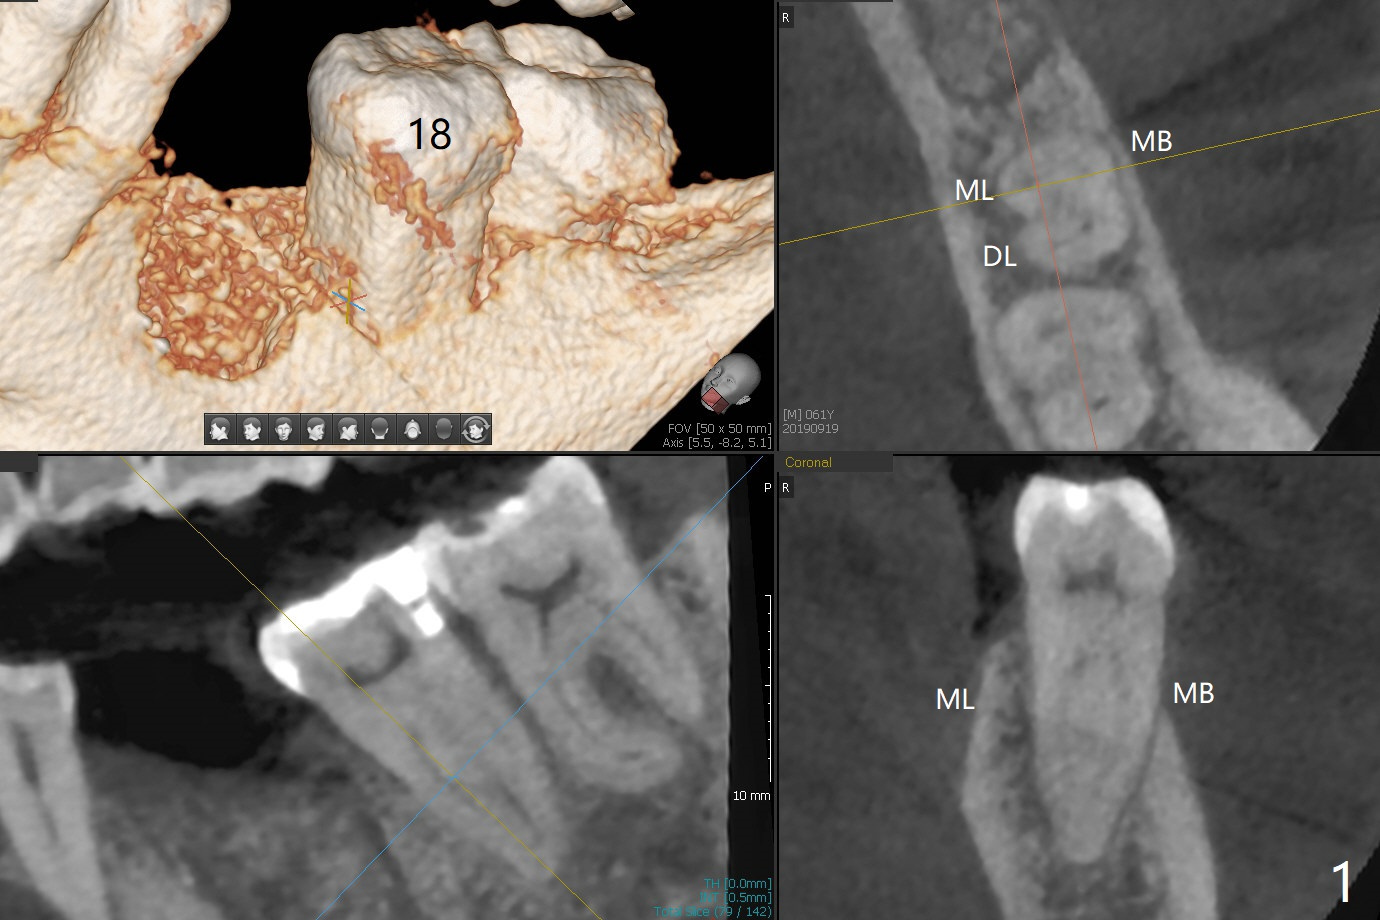

A 61-year-old man may have referral pain between #17 and 18. The canals at #18 are narrower than those at #17 (Fig.1-3). If #18 needs RCT, blocks should be removed (Fig.4-6 vs. 4'-6').